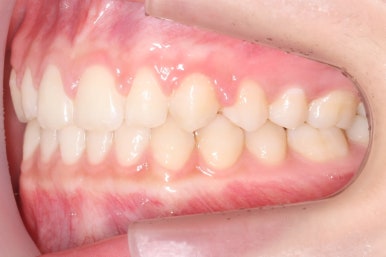

마무리 때의 사진입니다.

윗니만 부분교정하였지만 교합에도 이상 없이 매복되었던 송곳니는 매우 잘 위치를 잡았습니다.

송곳니 부위는 다시 틀어지지 않게 하기 위해 유지철사를 붙여주었습니다.

총 치료기간은 20개월 소요 되었습니다.

부산매복치아교정 상악 부분교정을 통해 매복치를 교정해준 이번 치료의 전후사진 비교입니다.

썩은 유치 대신 영구치 송곳니는 매우 자연스럽게 위치되었습니다. 아랫니는 교정하지 않았기 때문에 약간 삐뚠 느낌은 남아있지만 맞물림은 크게 문제가 없게 마무리 되었습니다.